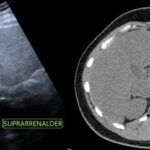

Se presenta el caso de un paciente masculino de 18 años sin antecedentes, que consulta por dolor en hipocondrio derecho de un año de evolución, asociado a palpitaciones, y episodios de HTA. El examen de orina de 24 horas mostró niveles elevados de catecolaminas. En la ecografía abdominopélvica y TAC abdominal, se objetiva una formación de aspecto nodular sólida hipoecoica de contornos bien delimitados, de aproximadamente 43 mm x 39 mm, que no muestra vascularización a la señal Doppler color, asociado a la TC abdomen con contraste EV: masa sólida de 38 mm x 31 mm, reemplazando el parénquima de la glándula suprarrenal derecha que realza de forma ávida y heterogénea en fase arterial a expensas de área central con degeneración necrótica. Se prepara con alfa bloqueador, se realiza adrenalectomía total izquierda laparoscópica. La anatomía patológica evidencia feocromocitoma.

El feocromocitoma es una entidad que afecta a pacientes jóvenes y tiene diversos hallazgos imagenológicos, siendo los más característicos por ecografía como masas grandes sólidas o quísticas con calcificaciones, de bordes bien definidos, dependiente de una glándula suprarrenal, en la TAC suelen ser heterogéneas, frecuente la calcificación, hemorragia y necrosis, con marcado realce tras la administración de contraste. Siendo este el gold standard con el protocolo de lavado suprarrenal se compone de una fase sin contraste, una exploración contrastada con un retraso de 60-90 segundos y una tardía a los 15 minutos con densidad > 10UH.